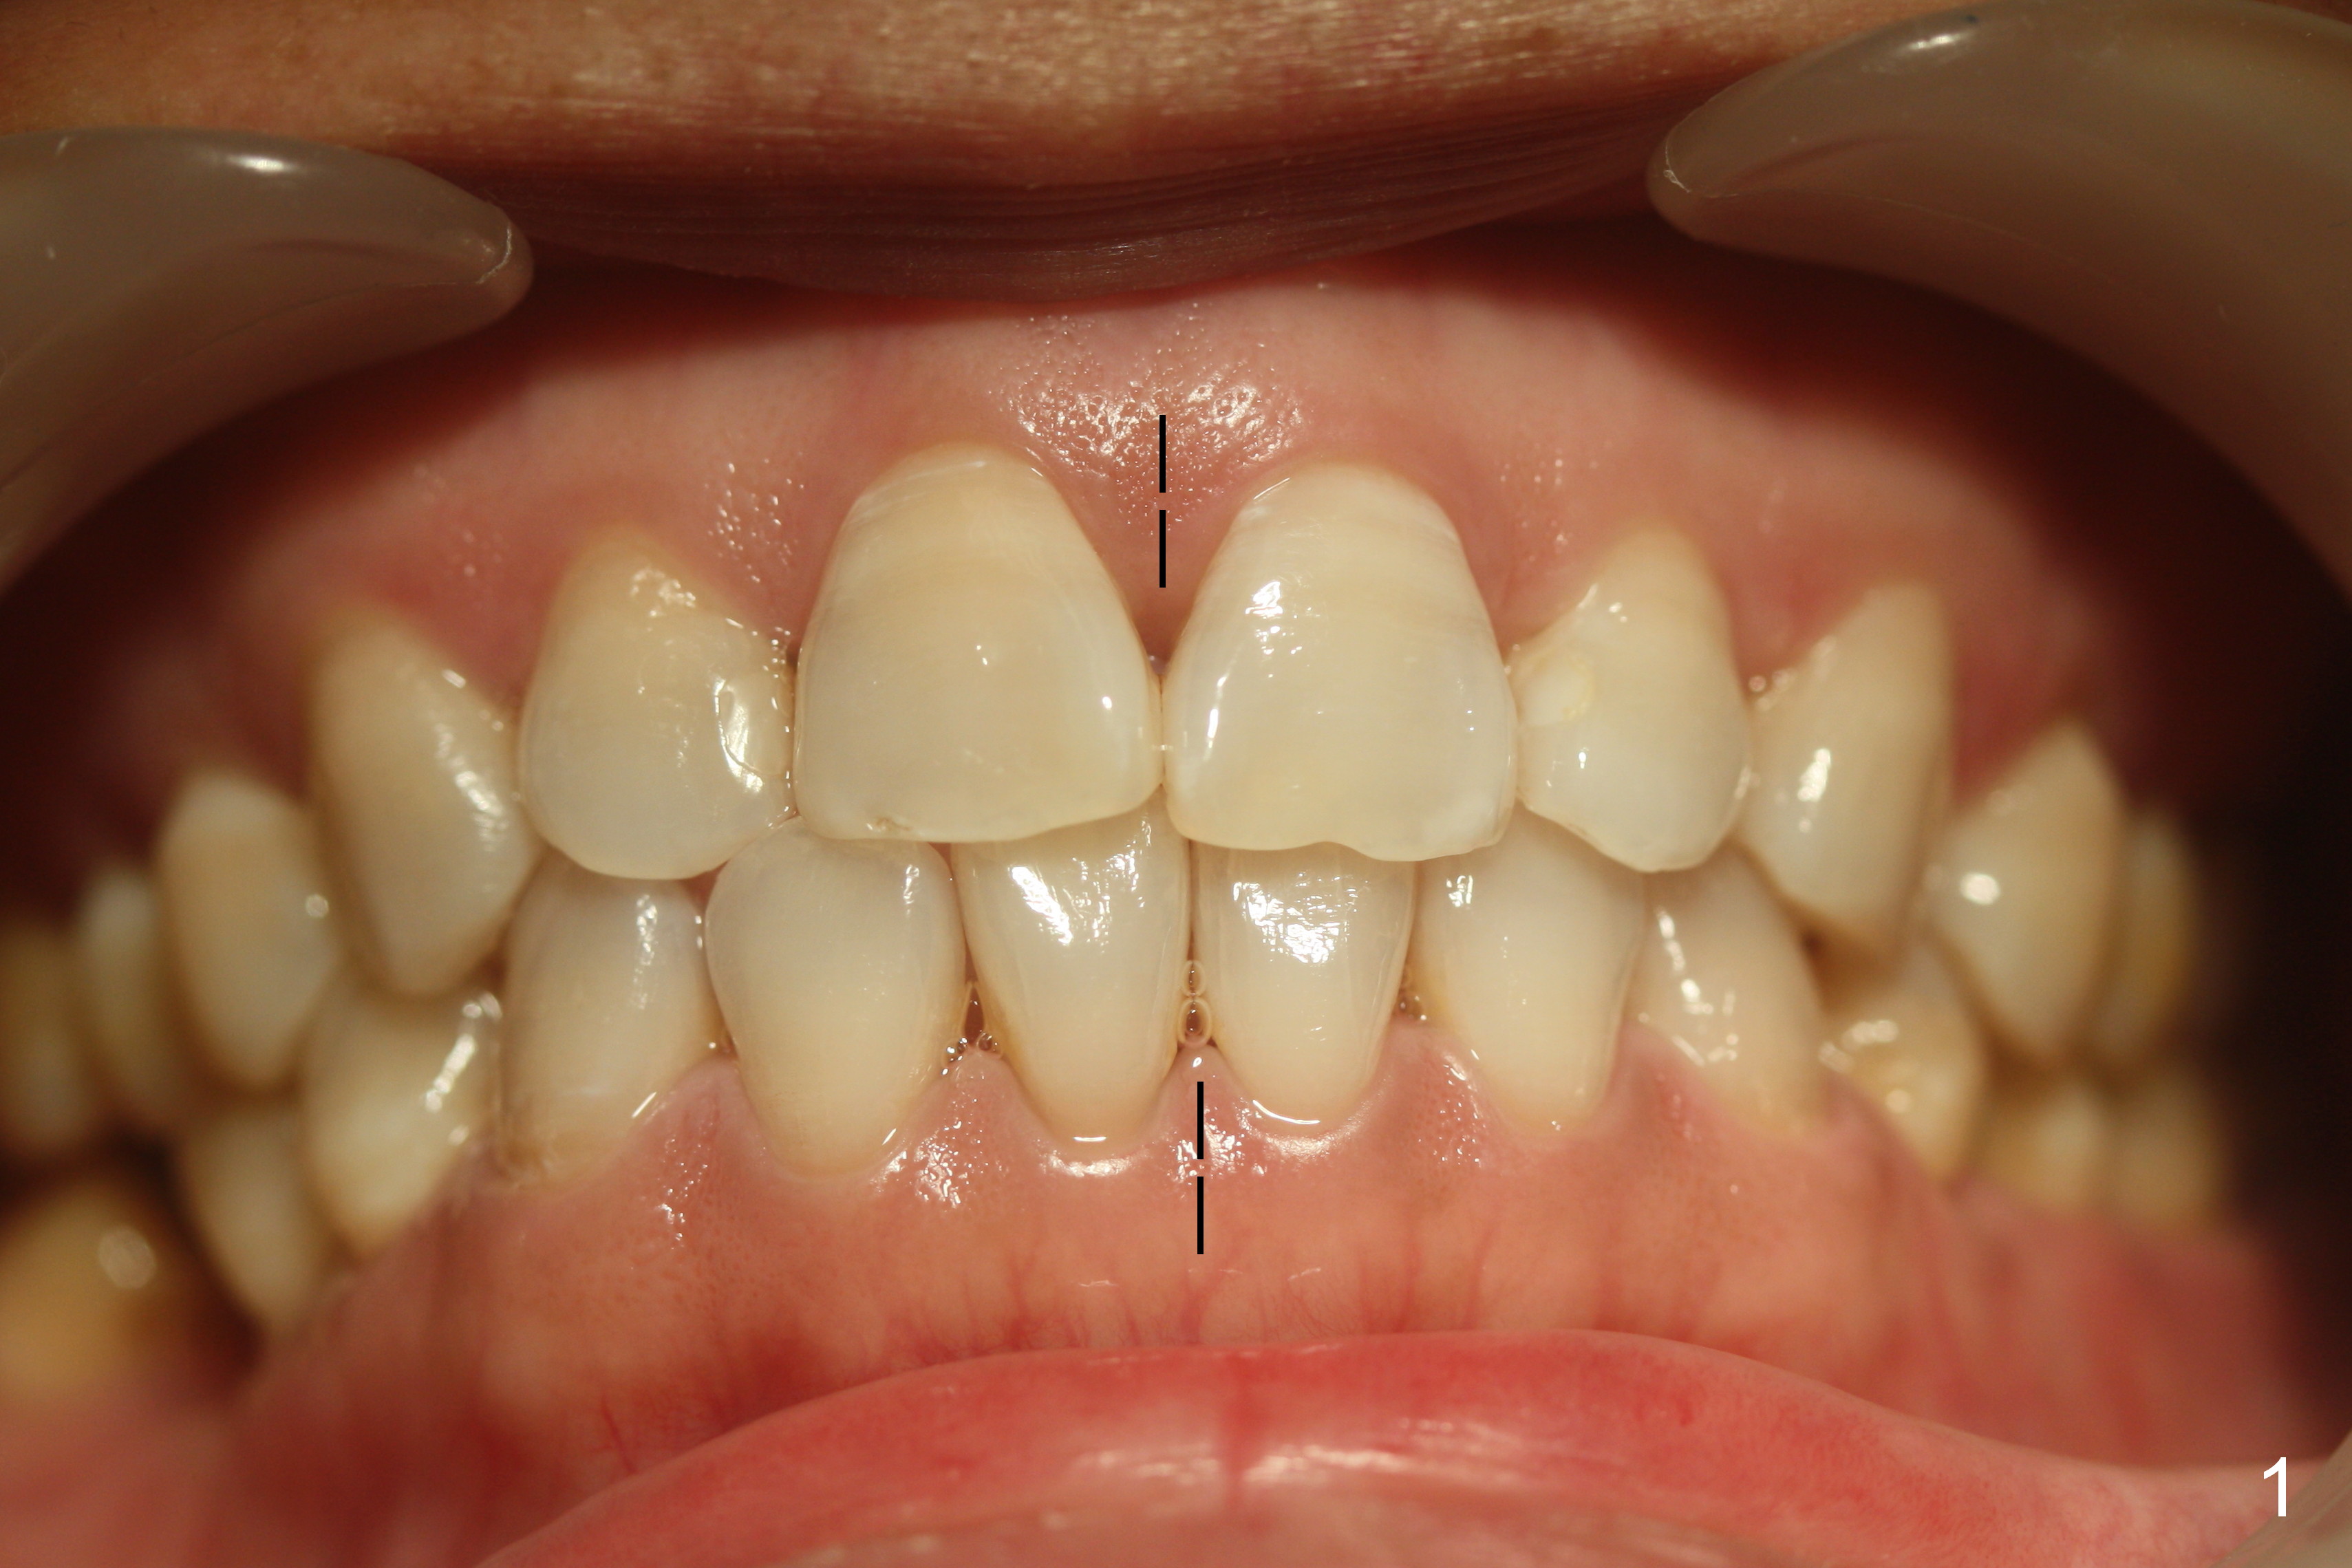

A 38-year-old woman agrees with implant placement at #30 and orthodontic preparation, but she does not like to have the tooth #32 extracted (Fig.7).

Show the patient that the tooth #31 is severely mesially tilted with reduction in the mesiodistal width for implant placement (Fig.5,7). The tooth #32 is severely malpositioned (linguoversion, Fig.6). It is extremely difficult to gain space for the implant without #32 extraction.

Four weeks of using open coil spring between #29 and 31, these teeth seem to have rotated (Fig.8,9 curved arrows). After placing a longer spring and the same arch wire, power chains are installed to close the anterior diastema (Fig.10 ^). The patient notes the divergence between #20 and 21 (Fig.11). To correct the latter, either place #20 bracket more distal (Fig.11 *) or place power chains between these teeth only. To facilitate #31 distalization (Fig.13), place lingual buttons (Fig.12 red) in the mesial surface of #31 and the distal of #2 with an elastic between the buttons.